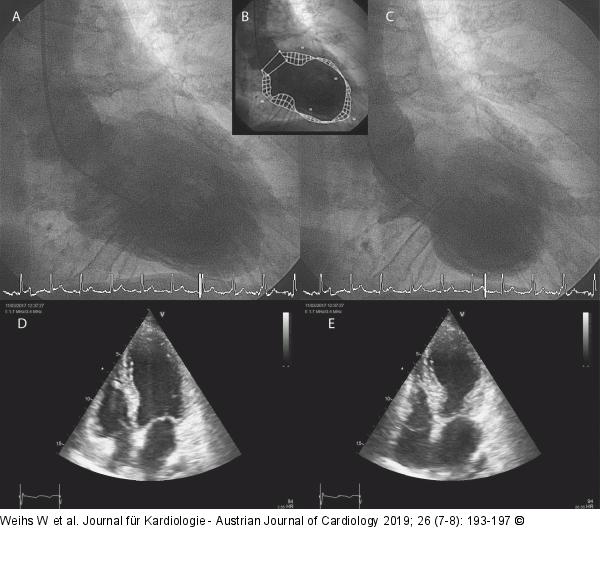

Abbildung 4A-E: Laevokardiogramm - Echokardiogramm (A): Laevokardiogramm enddiastolisch; (B): Kontur; (C): Laevokardiogramm endsystolisch; (D): Echokardiogramm enddiastolisch; (E): Echokardiogramm endsystolisch |

(A): Laevokardiogramm enddiastolisch; (B): Kontur; (C): Laevokardiogramm endsystolisch; (D): Echokardiogramm enddiastolisch; (E): Echokardiogramm endsystolisch |